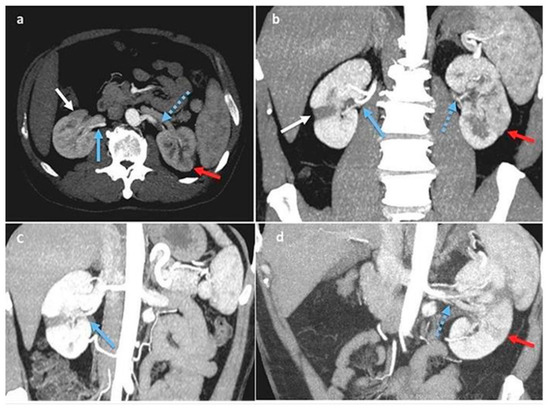

Aiming for a vessel disease diagnosis, computed arteriography with selective renal and polar artery catheterization [2] was performed as a second-level instrumental exam.

This yielded many findings: On the right side, there was an occlusion of a small intraparenchymal terminal branch of the right renal artery, while the inferior polar artery on the right remained patent. On the left side, a dissection of the middle third of the renal artery was observed, characterized by a false occluded lumen and a patent lumen supplying the intrarenal branches; the lower renal polar artery on the left side was also patent (Figure 2a,b).

Figure 2.

(a,b): Digital subtraction angiography (DSA). Right kidney (a): segmental renal artery occlusion (white arrow) consequent to distal dissection (blue arrows) of the inferior polar artery originating from the abdominal aorta. Left kidney (b): renal artery dissection (blue arrow with dots) with occlusion of smaller superior and inferior segmental branches and their corresponding focal de-vascularized areas (red arrows).